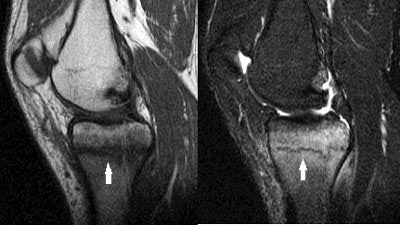

MRI revealed a linear signal abnormality oriented horizontally 2-3 cm inferior to the medial tibial articular surface. The linear signal abnormality was dark on both T1- and T2-weighted images, and was surrounded by a substantial amount of bone marrow edema.

| Sagittal T1 (left) and T2 (right) MR images reveal a linear signal abnormality oriented horizontally inferior to the media tibial articular surface (white arrows). The signal abnormality indicating the fracture line is dark on both T1- and T2-weighted images. |